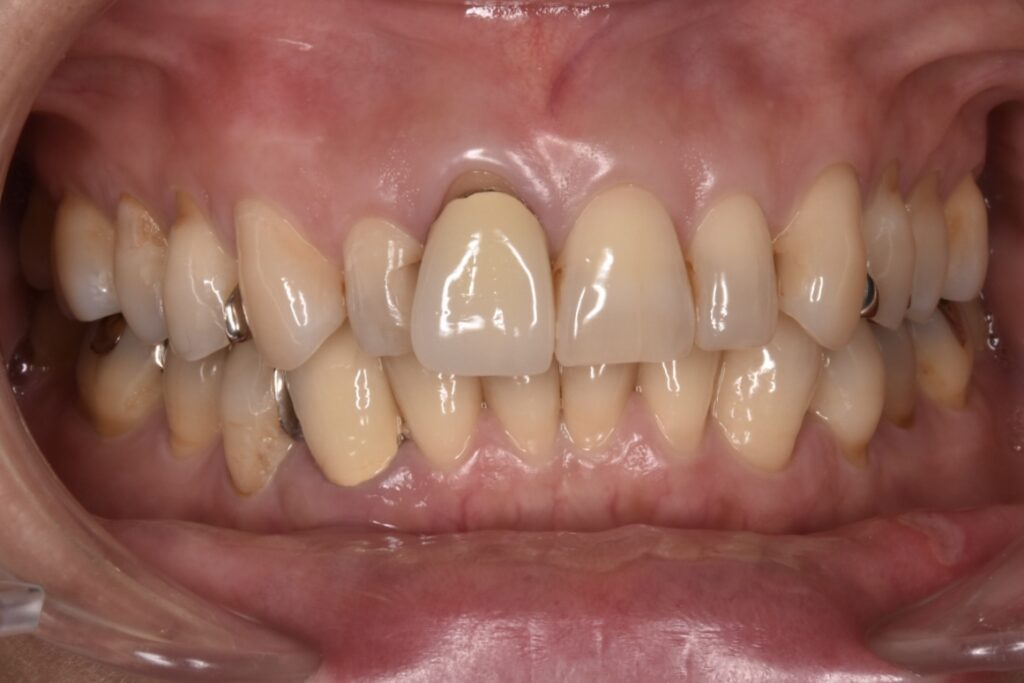

モニター様①

こちらのお客様は全ての銀歯と古い被せ物をやりかえしてくださったモニター様です。上の前歯と下の歯の犬歯がよくわかります。見える部分の銀歯も無くなりました。*ダイヤモンド匠プラン